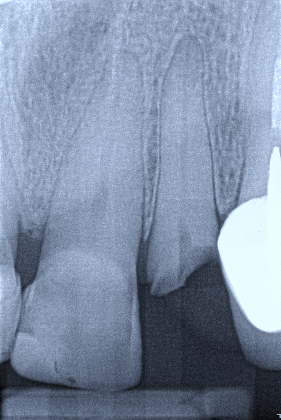

Which of the following may complicate the extraction of tooth 1.3?

Which of the following may complicate the extraction of tooth 2.5?

Which of the following may complicate the extraction of tooth 2.2?

Which of the following may complicate the extraction of tooth 1.4?